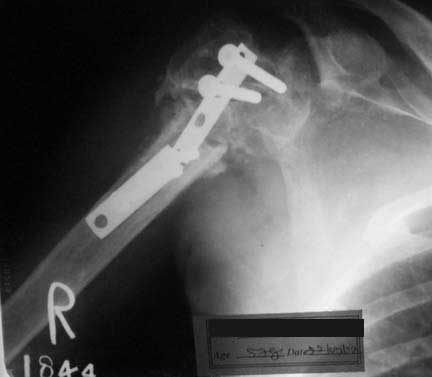

56 year old gentleman presented with pain right upper arm and difficulty in lifting right arm. Gives history of injury two years ago following which he was operated elsewhere.(Two surgeries, the first for fixing the fracture and second for reinserting screws which pulled out).Inability to use right upper limb ever since. History of chronic alcoholism and smoking. Examination reveals two scars in the anterior part of right shoulder. Movements at right shoulder grossly restricted with pain and minimal abnormal mobilty. X-ray and clinical picture attached.

I would remove the broken hardlware, assess for infection (and treat infection if present with irrigation/debridment), and then refix. If you have it available, Synthes makes a blade plate that would be ideal since it would provide fixed angle fixation in the head. Alternatively standard compression plating could be used. A 3.5 DCP (or LC-DC) can be bent and can also used as a blade plate. I would bone graft at the same time. (On my screen, the x-ray is pretty dark, and i can't tell the condition of the humeral head or tuberosities. The title of the e-mail says that the head is collapsed. If that is the case, the alternative would be hemiarthroplasty with careful reattachment of the tuberosities, and again assessing carefully for infection.)